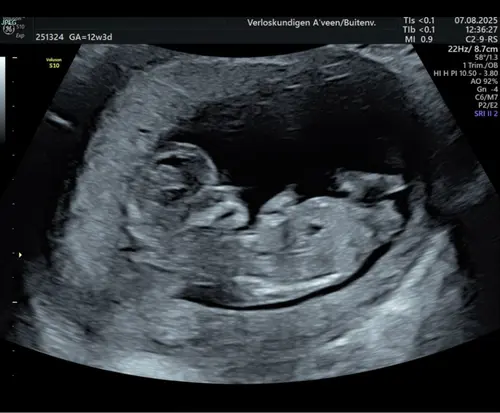

Kan iemand er iets van maken? Echo bij 12 + 6

Vandaag precies 13 weken en de echo gehad! Al willen wij het tot het einde niet weten wat het wordt, ben ik toch benieuwd wat jullie denken te zien! ☺️ Gewoon voor later om te zien of het klopte 😉

Hier 13+2, iemand een idee? 🩵🩷